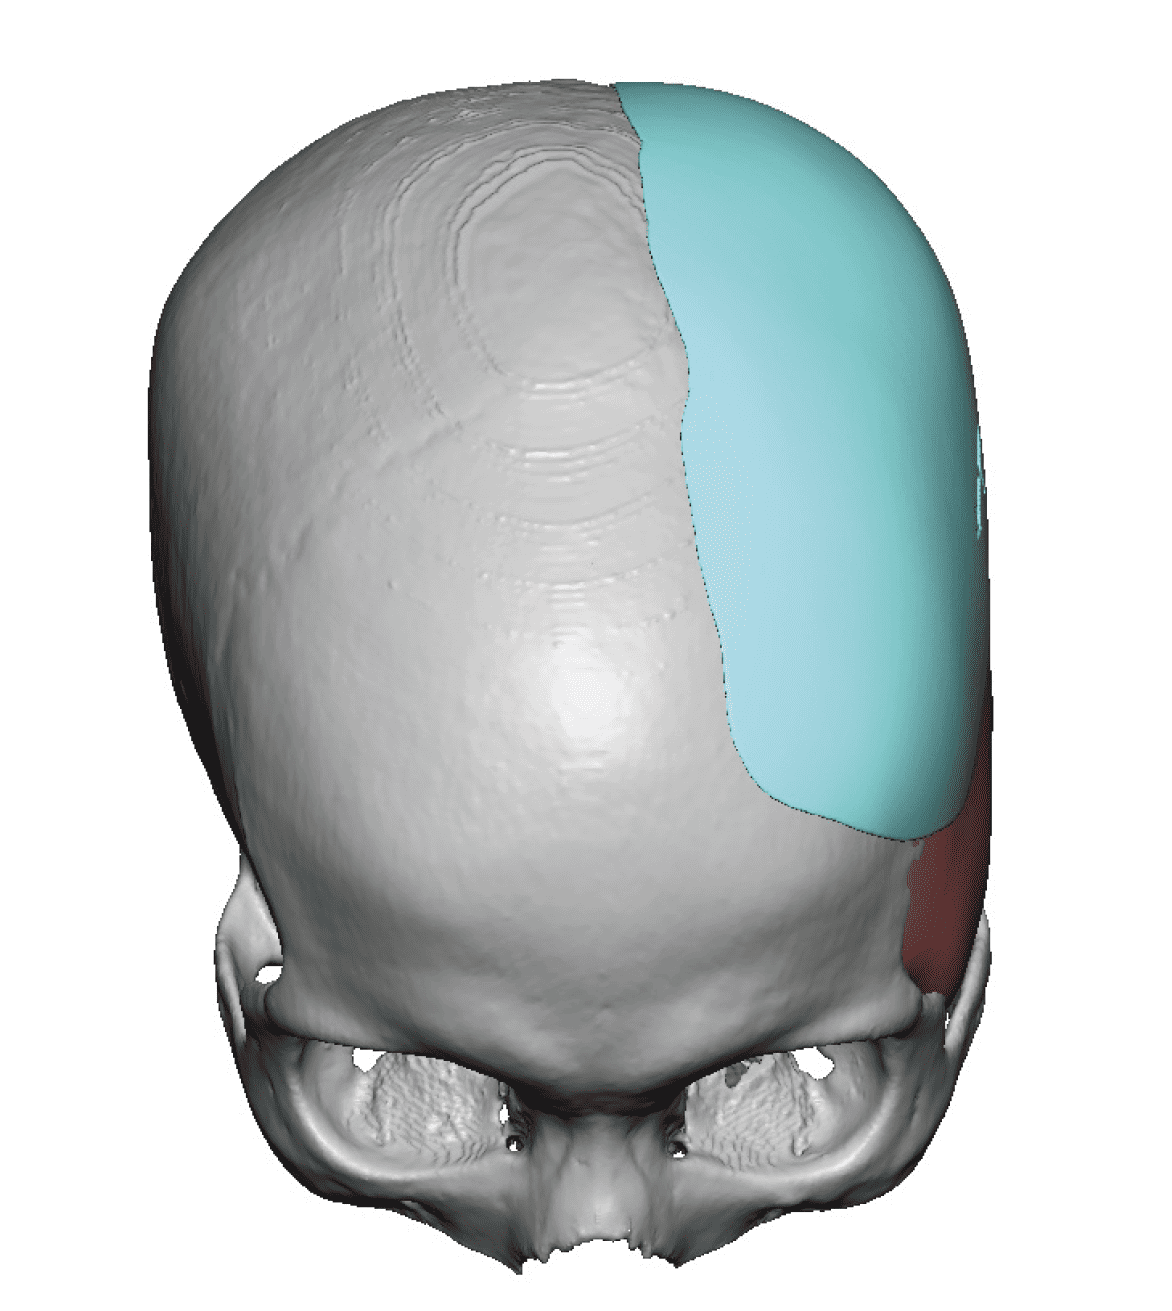

Patient 84

Desire for change of head shape from front view form an inverted V shape to a rounder and wider head shape.

Placement of custom extended forehead-temporal implants through incisions in the crease behind the ear. (he had a prior back of head skull implant which is green in the implant designs and which the head widening implants partially covered it)

Desire for change of head shape from front view form an inverted V shape to a rounder and wider head shape.

Placement of custom extended forehead-temporal implants through incisions in the crease behind the ear. (he had a prior back of head skull implant which is green in the implant designs and which the head widening implants partially covered it)